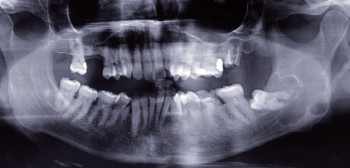

Article réservé à nos abonnés Nerf alvéolaire inférieur

Le fait que l’extraction des dents de sagesse mandibulaire soit désormais une pratique courante peut s’expliquer en partie par les...